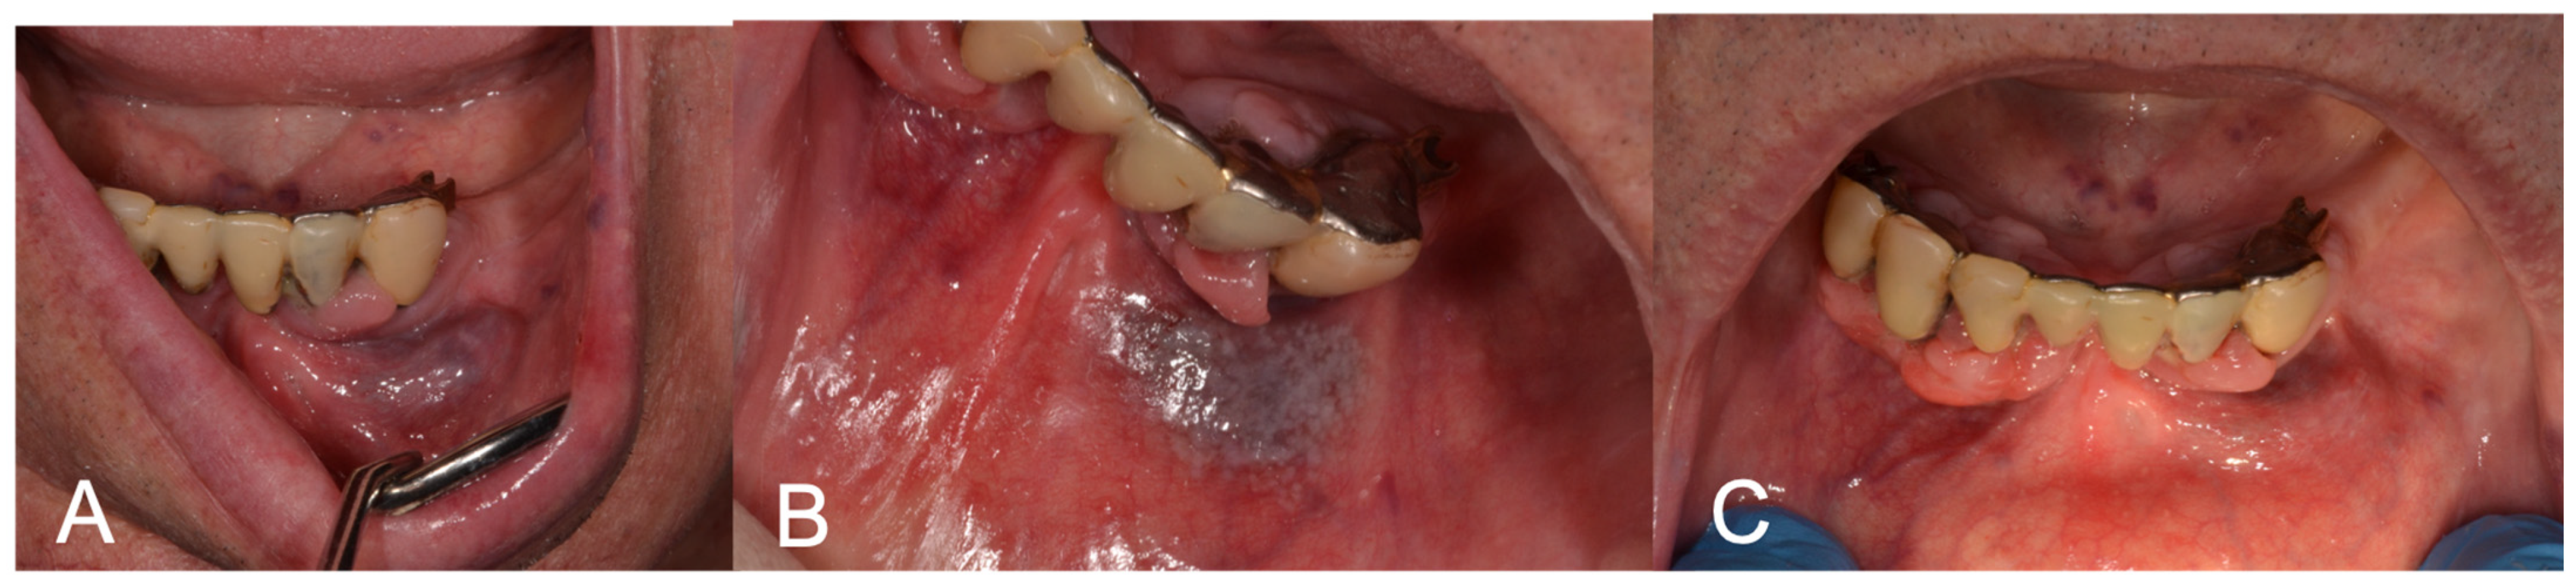

Figure 2.

(A) Preoperative aspect of gingiva and lip VM; (B) LFD; (C) 3-week follow-up showing complete healing after LFD.